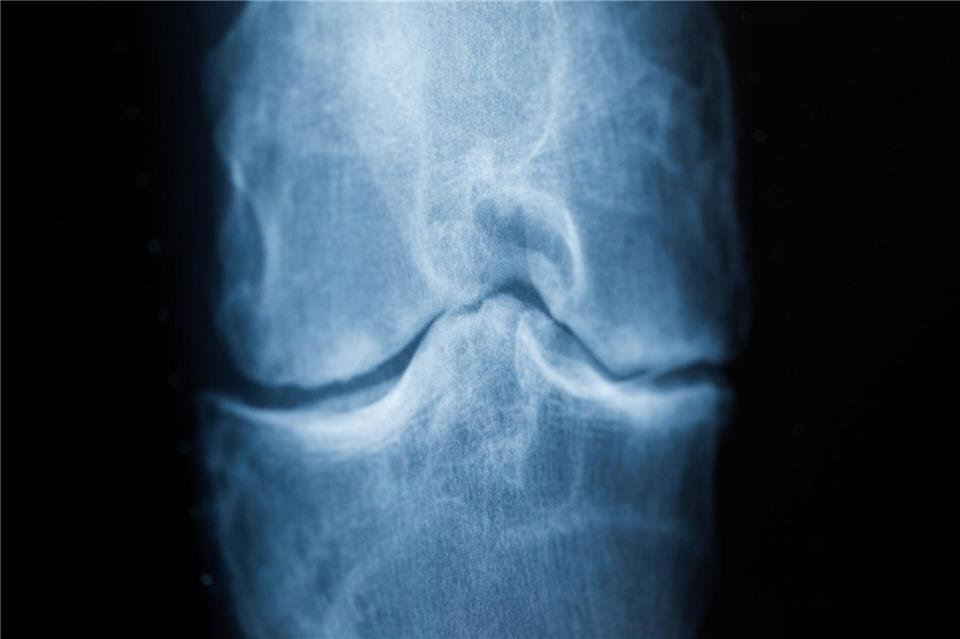

Rheuma kann sich durch Schmerzen etwa im Knie bemerkbar machen. (Archivfoto)Rolf Vennenbernd/dpa/dpa-tmn

Gerade bei entzündlichen Rheuma-Erkrankungen spielt der Faktor Zeit eine große Rolle. Eine möglichst schnelle Diagnose und damit verbunden ein möglichst schneller Therapiestart kann bleibende Schäden an Knorpeln und Knochen verhindern, wie Schwarting, der auch ärztlicher Direktor des Rheumazentrums Rheinland-Pfalz ist, erklärt.